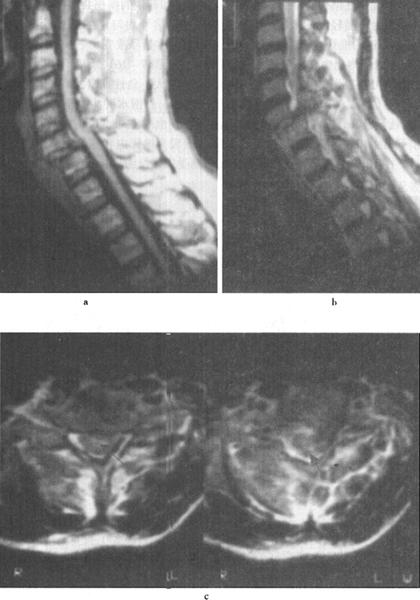

(4)脊髓受压:脊髓受压变扁变形,局部脊髓信号强度可正常或T2WI信号轻度增高(图7-17)。通常是由于脊柱骨折和脱位,使椎管变形、狭窄所造成,多见于椎体的爆裂性骨折、过屈过伸性损伤、旋转性创伤和单纯的压缩性骨折等,这些创伤往往伴有严重的肌腱和韧带损伤。

图7-17 T12压缩性骨折并脊髓横断性损伤:T1W(a)和T2W(b)矢状面扫描,可见T1压缩变扁,T11以上向前移位,脊髓呈横断性改变。椎间盘及脊柱前纵韧带下血肿。冠状面脊柱两侧亦见高信号出血

(5)脊髓横断:脊髓横断表现为脊髓和硬膜囊连续性中断,在矢状面显示清楚。完全性横断可伴有脊髓的回缩,两断端出现较宽的间隙。MRI检查T2WI较T1WI敏感,可清楚显示横断的脊髓,尤其是在T2WI,脑脊液呈高信号,而脊髓呈中等信号,两断端间充满高信号的脑脊液(图7-18)。不完全性脊髓横断,在T2W呈高信号,脊髓连续性尚存。

图7-18 T11椎体骨折脱位伴脊髓横断性损伤:T1W(a)和T2Wb矢状面示,T10以上明显向前脱位,椎管和脊髓在T11水平中断和成角,脊椎前、中、后柱骨折脱位,并有脊柱周围血肿